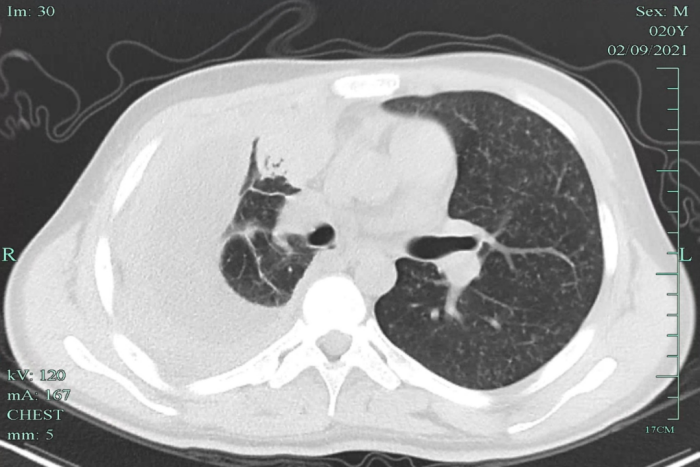

在當(dāng)?shù)蒯t(yī)院檢查,發(fā)現(xiàn)小明兩肺粟粒影,提示可能血行播散性肺結(jié)核,伴有胸腔積液,提示病程比較長(zhǎng)了,炎癥反應(yīng)嚴(yán)重。小明立即來到我院感染科就診,隨后住院治療。

經(jīng)全面檢查,小明被診斷為“急性血行播散性肺結(jié)核、結(jié)核性滲出性膿胸”,該類型的肺結(jié)核非常容易引起其他部位的結(jié)核播散,雖然當(dāng)時(shí)小明沒有頭疼頭暈癥狀,但經(jīng)過頭顱磁共振檢查發(fā)現(xiàn),其顱內(nèi)有散發(fā)的結(jié)核病灶。